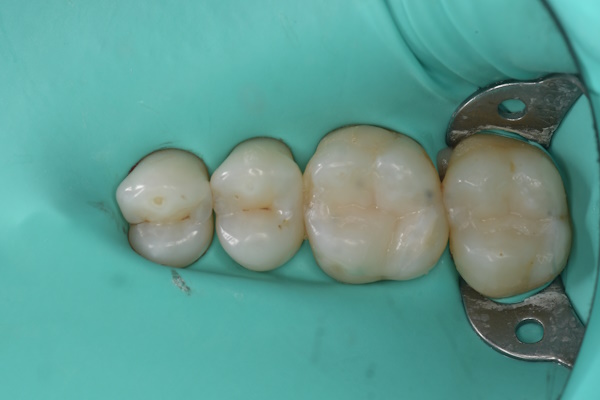

- 治療内容 セラミック治療(アンレー)

- メリット 審美性に優れており、天然歯に近い自然な色や形に仕上がります。金属を使わないため、金属アレルギーの心配がなく、高い適合精度と耐久性によって、美しさと機能を長く維持しやすくなります。

- リスクと副作用 セラミック治療は保険適用外(自由診療)です。強い衝撃や過度な力が加わると、まれに割れることがあります。治療後にしみる症状がみられることがありますが、多くは時間とともに落ち着いていきます。

セラミック治療の治療例です。奥歯の虫歯を、見た目もきれいな材料で治したいとのご希望で来院されました。当院にて、2本同時にセラミック治療を行いました。接着効率を高めるため、ラバーダムを使用しています。オキシガードは、過酸化物と還元剤による化学重合反応により、歯科接着用レジンセメント表面の未重合層を硬化させる材料です。さらに、未重合層を空気から遮断することで、確実な硬化を促します。

術前から術後までの治療の流れ

セット後